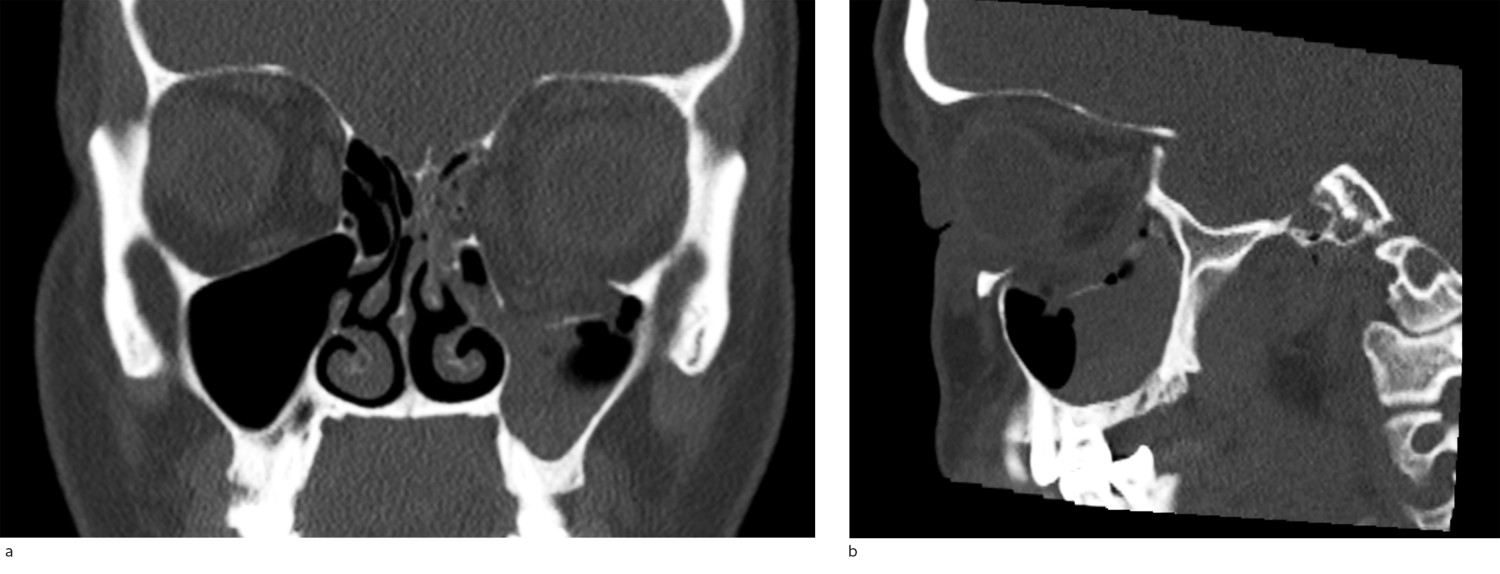

CT er foretrukket bildediagnostisk undersøkelse for å avdekke orbitafrakturer. Ved mistenkt fraktur bør det rekvireres CT av ansiktskjelett med tynne snitt (1 mm). Denne kan avdekke frakturens lokalisasjon, størrelse og eventuell påvirkning på ekstraokulær muskulatur (figur 3a og 3b). I tillegg kan man se om det foreligger mulig trykkgivende hematom i relasjon til frakturen. Man kan også vurdere bulbus' posisjon og om det foreligger proptose (eksoftalmus, utstående øye) på de aksiale snittene. Dette kan i noen tilfeller være vanskelig å vurdere klinisk ved uttalt periorbital hevelse.